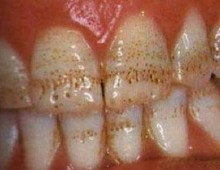

- Orális és fogászati diagnózisa anomáliák vagy hibák (például, az azonosítás a csont zsebek, ízületi betegségek, mértékének meghatározására ínybetegségek);

- felfedve rejtett pulpa betegségek, fogak, az íny;

- üregek a szájban;

- Ez lehetővé teszi, hogy diagnosztizálni, ahol a hagyományos diagnosztikai módszer sikertelen (rejtett fogszuvasodás, csont tumorok, és mások.), Ahol fontos, hogy ne hagyja ki az elején a betegség.